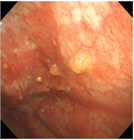

1. 胸腔鏡で腫瘍が確認されない最も早期の胸膜中皮腫である”mesothelioma in situ(前浸潤性中皮腫)” の存在は以前から知られていたが、『WHO分類 第5版』に初めて明記された。

1. 早期の胸膜中皮腫と反応性中皮細胞増生(反応性中皮過形成)の病理像は類似し、良悪の鑑別は慎重に行う必要がある。BAP1免疫染色、CDKN2A遺伝子の中皮腫でのホモ接合性欠失の検出が鑑別に役立つ。